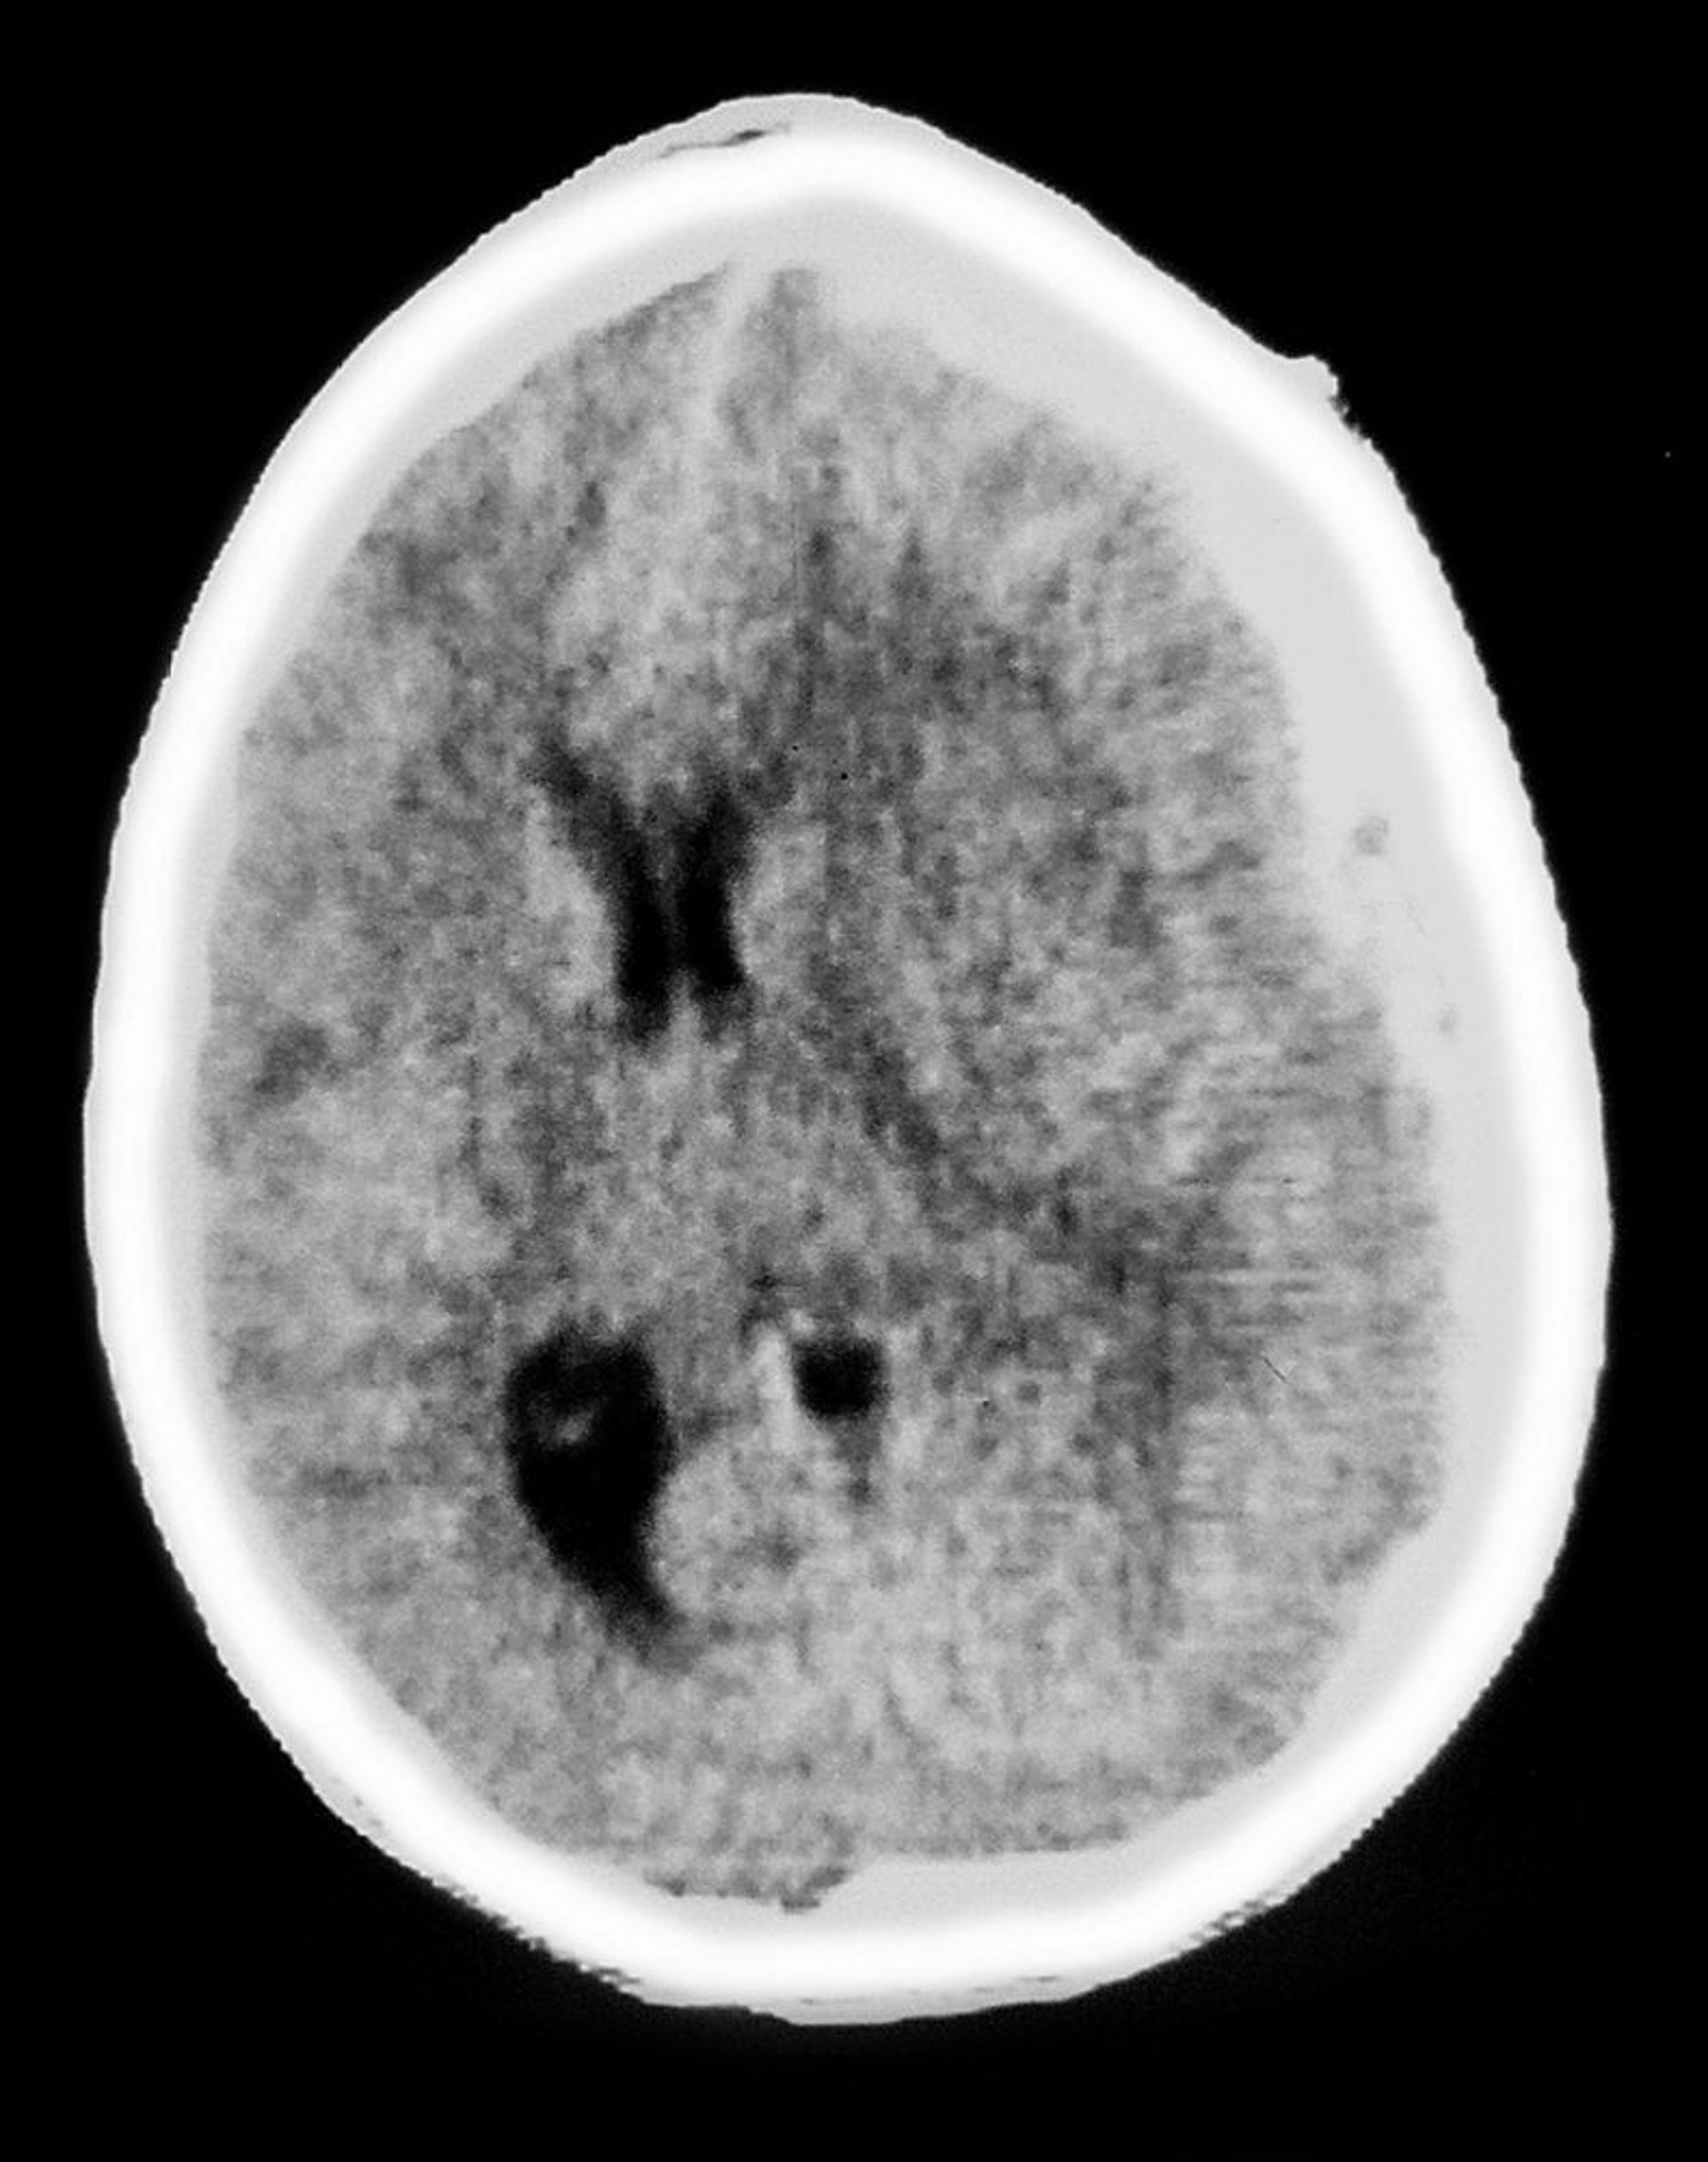

Hématome sous-dural

Cette TDM montre une opacité en forme de croissant recouvrant le tissu cérébral, caractéristique d'un hématome sous-dural. Il y a aussi un effet de masse, avec la compression ventriculaire et un déplacement de la ligne médiane.